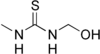

| Preferred IUPAC name

N-(Hydroxymethyl)-N′-methylthiourea | |

| C3H8N2OS | |

| Molar mass | 120.17 g·mol−1 |